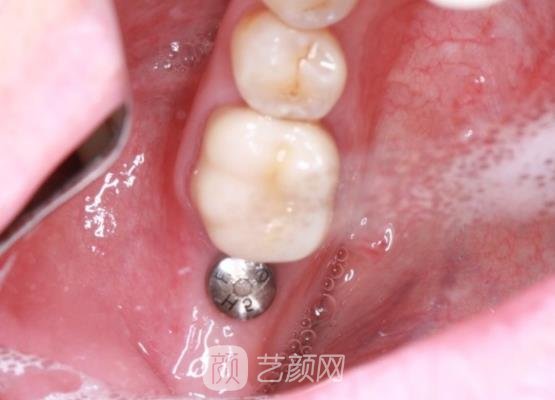

接下来就开始了手术,医生的手术手法是比较娴熟的,而且可能是因为采用了麻药的处理,手术过程中我也没有感觉到剧烈的疼痛感,手术完成的也是比较快的,几个小时就结束了。

刚结束手术的时候,因为我的牙齿有一些肿胀的情况,还很疼,所以我也比较担心,就询问了医生,医生告诉我这些现象比较正常,几天以后就会自动消退,并且告诉我如果有异样的情况,让我及时的与他取得联系进行复诊。

几个月以后,我的种植牙已经恢复好了,看起来就像是我自己的牙齿一样,手术真的是比较有成果的,现在我整个人都比之前漂亮了很多,这项手术真的方便了我的生活。